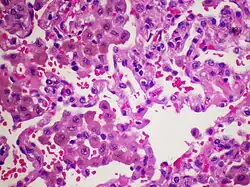

Alveoli are filled with macrophages, many containing golden brown tobacco pigment.

The major hallmark of DIP is the presence of a large number of macrophages within the alveoli that are distributed throughout the pulmonary acini. These macrophages are rich in eosinophilic cytoplasm and frequently include a coarsely granular light-brown pigment. There are usually a few multinucleated large cells. The alveolar architecture is typically intact, however there is a modest chronic inflammatory infiltration inside the interstitium. A moderate quantity of eosinophils might also be present. Lymphoid aggregates can be present.[18]